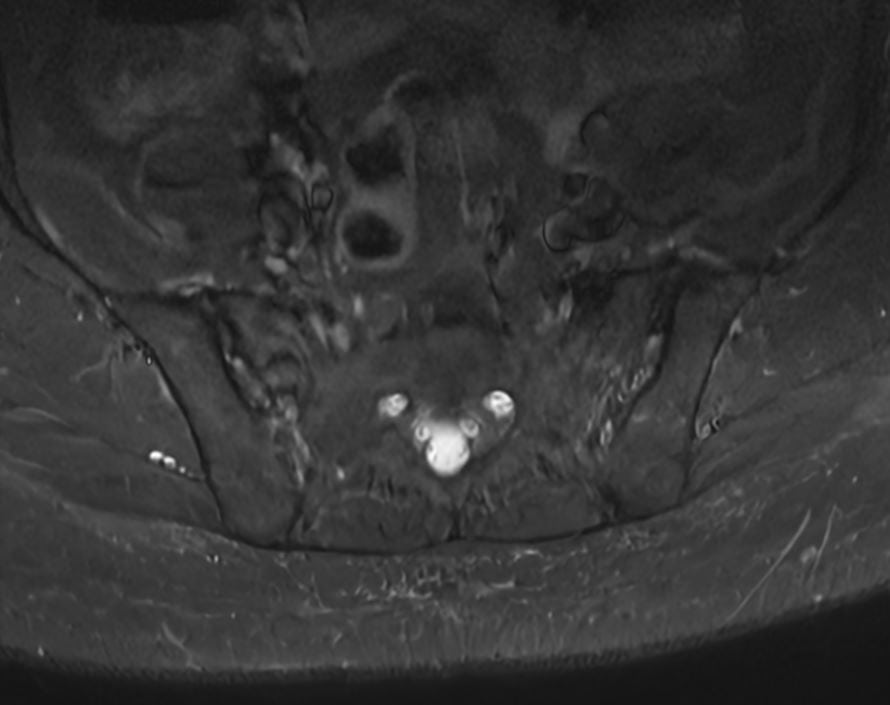

Få præcis diagnose af dine SI-ledsmerter med avanceret MR-scanning hos Progardia. Vores kraftfulde 3 tesla scanner giver ekstraordinært detaljerede billeder af sacroiliacaleddet, hvor rygsøjlen møder bækkenet. Oplev markedets mest nøjagtige visualisering af inflammation, artrit og andre forandringer, der ofte overses ved konventionelle undersøgelser.

En MR-scanning af SI-led (sacroiliacaled) er en avanceret, smertefri undersøgelse, der giver detaljerede billeder af forbindelsen mellem korsbenet (sacrum) og hoftebenet (ilium).

Vores 3 tesla MR-scanner bruger et kraftigt magnetfelt og radiobølger til at skabe præcise billeder af leddet, omkringliggende knogler, brusk, ledbånd og bløddele – helt uden brug af røntgenstråling.

SI-leddet er et komplekst led, der ofte er svært at undersøge med konventionelle metoder. MR-scanning kan vise tidlige tegn på inflammation, artrit, slidgigt og andre forandringer, der kan være årsag til lænde-, hofte- eller bækkensmerter. Denne undersøgelse er særligt værdifuld ved mistanke om inflammatoriske rygsygdomme som f.eks. ankyloserende spondylitis (Morbus Bechterew).

Eksempler på MR Scanninger